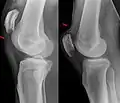

An x-ray demonstrating quadriceps tendon rupture. Note the abnormal angle of the patella and soft-tissue swelling marked by the arrow.

A quadriceps tendon rupture is a tear of the tendon that runs from the quadriceps muscle to the top of the knee cap.[1]